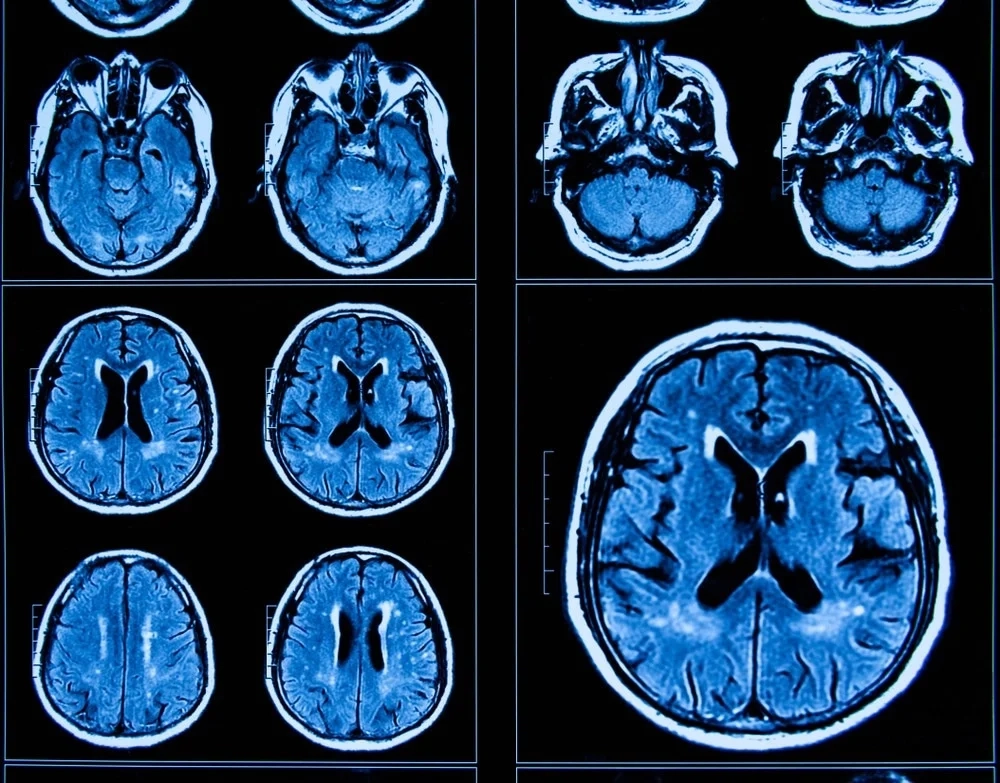

پژوهشگران دانشگاه ناتینگهام که هدایت این مطالعه را بر عهده داشتند، تصاویری از MRI 996 نفر که دوران COVID را پشت سر گذاشته بودند، ثبت کردند، مدل را اعمال کردند و “سن مغز” هر فرد را تخمین زدند؛ یعنی سن مغز آنها نسبت به سن واقعیشان.